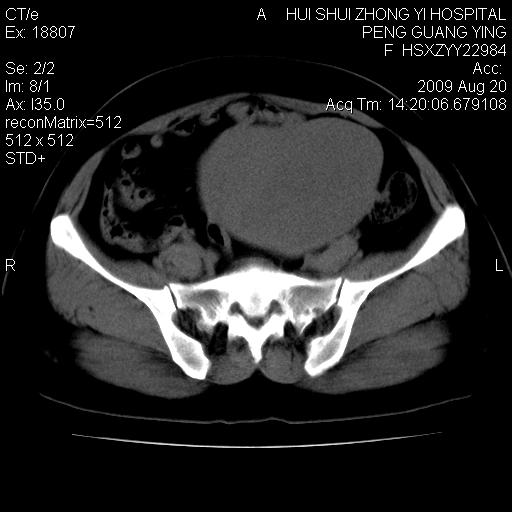

标题: CT21707:女,42岁,因发现下腹部包块2月。 [打印本页]

标题: CT21707:女,42岁,因发现下腹部包块2月。

目前的影像表现显示肿块位于腹腔及盆腔,但具体定位,分清来源较困难,是否来源于卵巢、子宫无法定论,子宫直肠及子宫膀胱周围脂肪间隙尚较清晰,如果患者有过腹腔好或者盆腔手术史,也可以形成不典型的血中,最好手术后定为定性,我期待结果。

软组织密度,与子宫一致。双侧卵巢形态、密度好,不支持来源于卵巢。